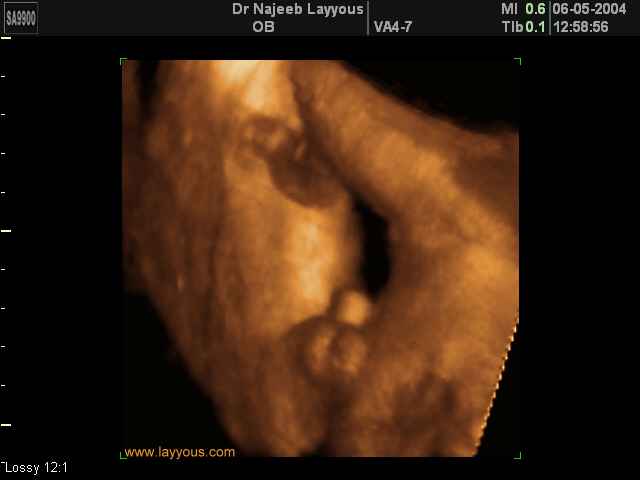

- 3D Photos échographie des parties du fœtus